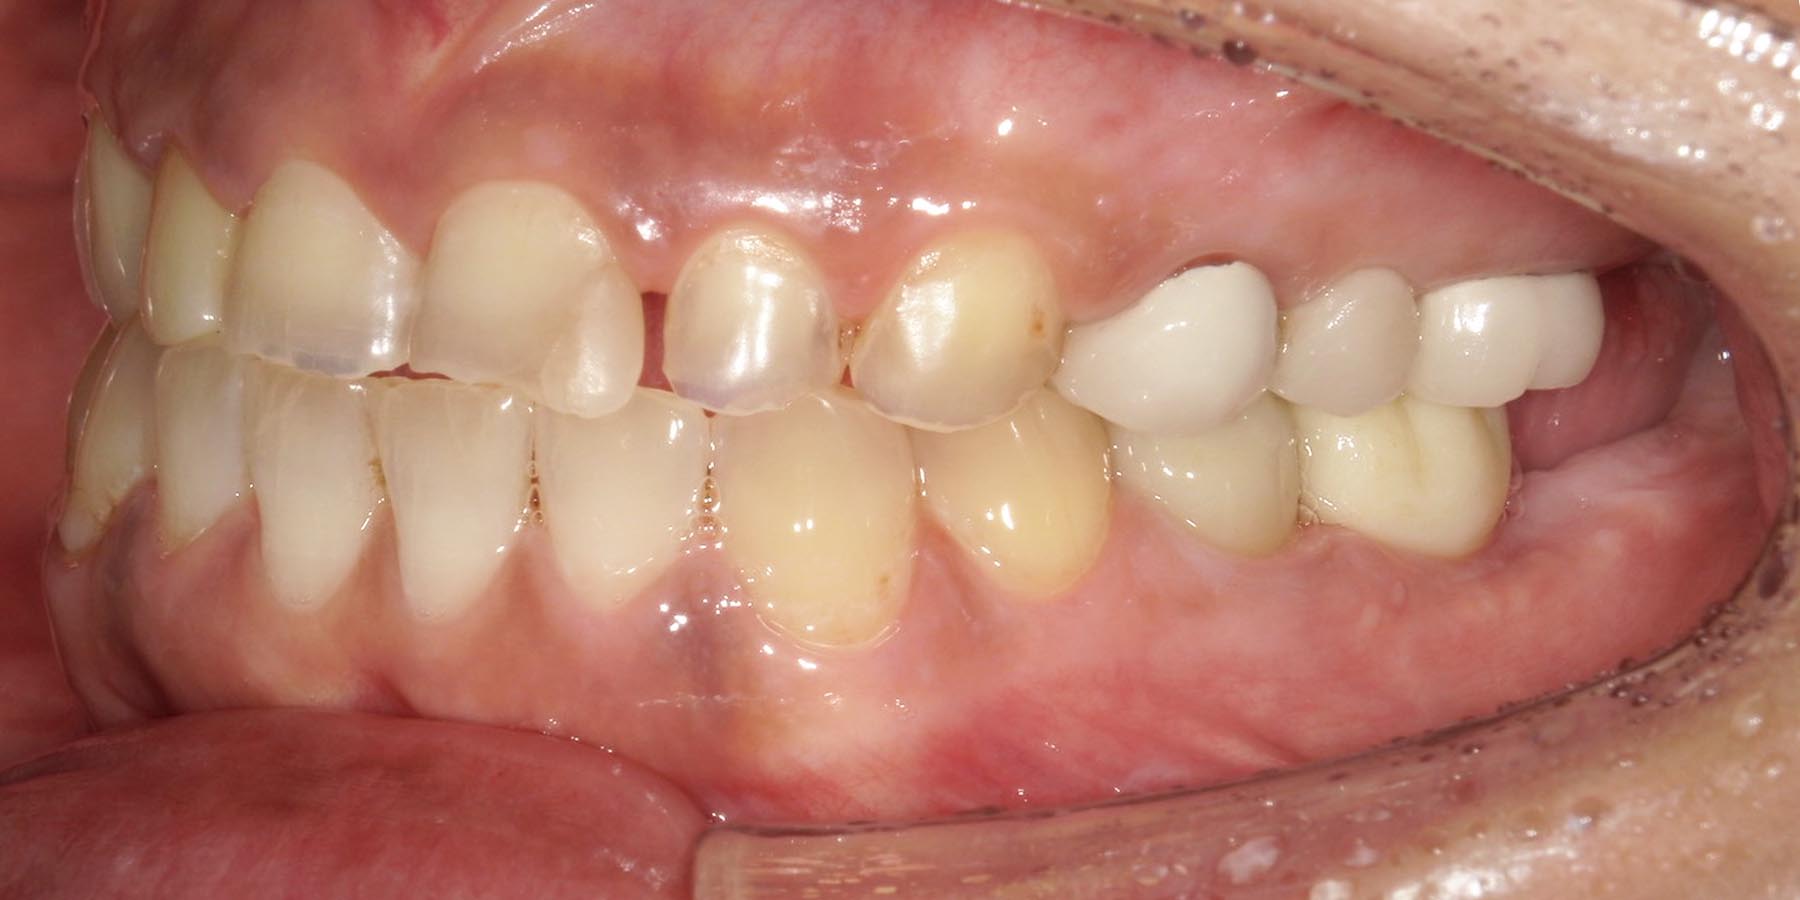

治療前

治療後